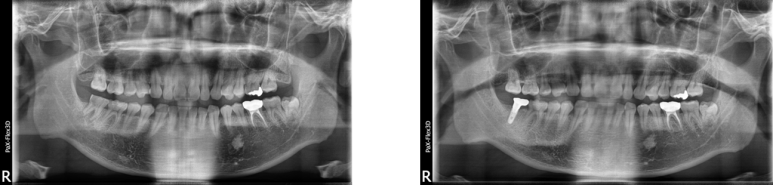

49세 남성

하악 임플란트 케이스

(전) 2021-08-18 (후) 2022-09-14

39세 남성

상악 임플란트 케이스

(전) 2021-12-07 (후) 2022-08-29